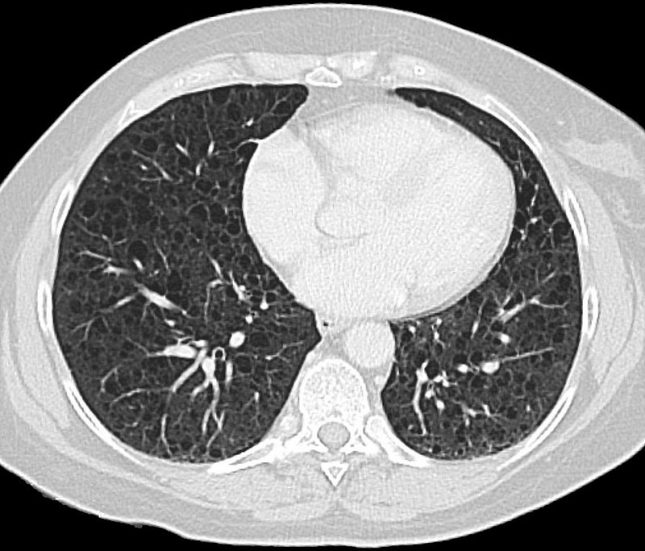

מחלת לִימפַאגיולֶיימִיומַאטוזִיס (LAM – Lymphangioleiomyomatosis) היא מחלה נדירה המופיעה אצל נשים. הירידה בתפקודי הריאות יכולה להיות מגוונת, מה שמוביל לקושי בהכוונת הטיפול. החוקרים השתמשו בפרוטאומיקה רנדומלית (unbiased serum proteomics) על מנת לזהות סמנים המקושרים לתוצאים ב-LAM.